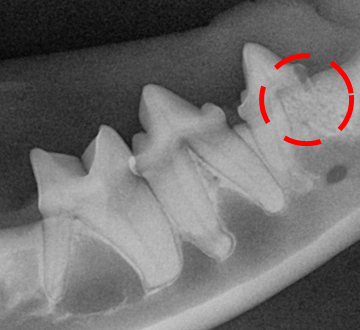

확인 결과, 방사선상 흡수병변이 발견되었습니다.

만약 치과 방사선을 찍지 않았다면,

407번 치아의 지속적인

통증에 시달렸을 것입니다.